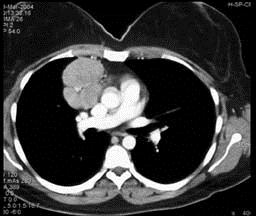

问题 女,27岁,双侧颈部淋巴结肿大,PPD(-),请结合CT图像,选择最可能的诊断 ( )

选项 A.心包囊肿 B.淋巴瘤 C.淋巴结核 D.转移性淋巴结肿大 E.结节病

答案 B